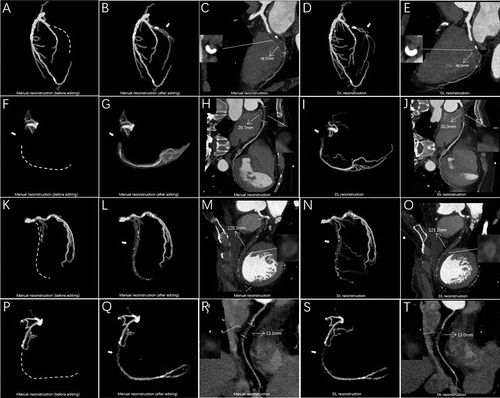

Emerging research revealed that a deep learning model had a nearly twofold increase in successful segmentation and reconstruction of coronary total occlusions (CTOs) on coronary computed tomography angiogram (CCTA) and a 73 percent reduction in post-processing and measurement time in comparison to a conventional manual approach.